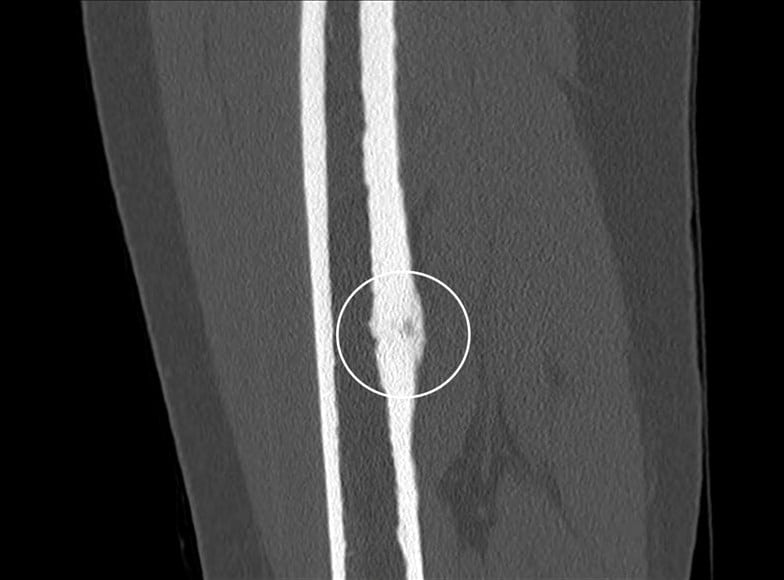

U dạng xương

» Thông tin: Nữ giới – 23 tuổi.

» Lâm sàng: Đau xương đùi 6 tháng.